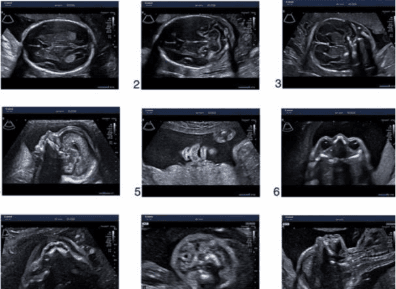

อัลตราซาวด์ 2 มิติ vs 4 มิติ ต่างกันอย่างไร? แบบไหนควรตรวจ?

อัลตราซาวด์ 2 มิติ (2D Ultrasound)

ภาพขาวดำ

เห็นเป็นภาพตัดขวาง (cross-sectional image)

อัลตราซาวด์ 4 มิติ (4D Ultrasound)

ภาพสามมิติแบบมีความลึก

เพิ่มมิติของเวลา (เห็นทารกเคลื่อนไหวแบบ real-time)

ภาพ | ขาวดำ ตัดขวาง | สามมิติ มีการเคลื่อนไหว |